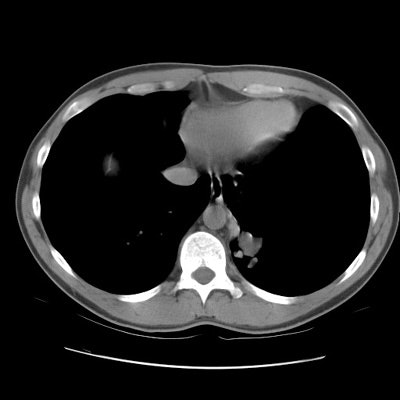

CT scan revealed a soft tissue mass in the left posterior-medial lung which had a branching tubular appearance. Some associated para-emphysematous changes were noted. (Click images to enlarge)